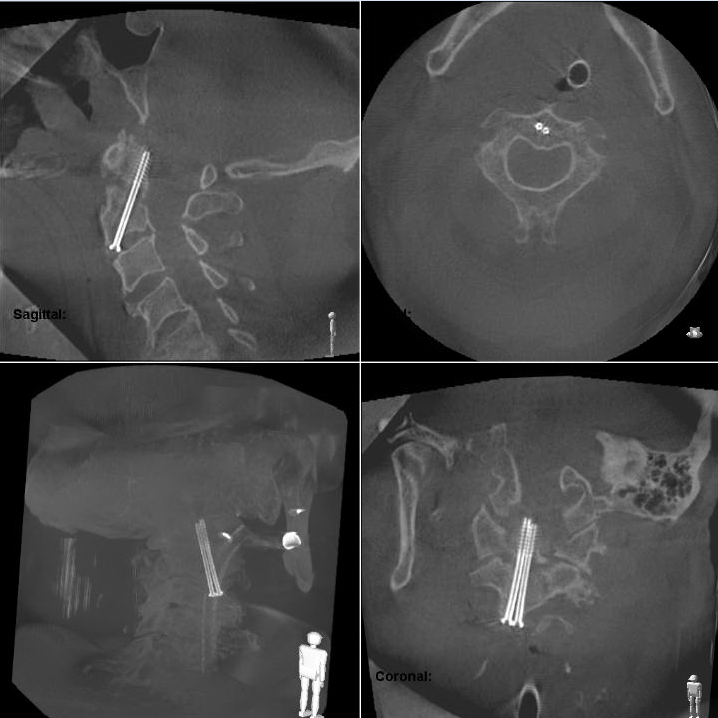

In einem klinischen Fallbeispiel beschreibt Dr. Jarvers eine instabile Dens Fraktur Typ II eines 67-jähriger Mannes: „Hier war die Indikation für eine schräge anteriore Verschraubung gegeben, die mit Ziehm Vision FD Vario 3D in Kombination mit Ziehm Vision RFD 3D durchgeführt wurde. Nach dem Setzen zweier Führungsdrähte unter fluoroskopischer Kontrolle wurden zwei kanülierte Schrauben nach der Smith-Robinson Methode platziert.“

Innerhalb von lediglich fünf Minuten wurde nach der Schraubenplatzierung ein intraoperativer 3D-Scan durchgeführt. Diese Zeit inkludiert neben der reinen 3D-Daten Akquirierung und Rekonstruktion auch die sterile Abdeckung des Patienten, die Einleitung der Hyperoxigenierung, den Atemstopp des Patienten, sowie die Zeit, die das OP Personal benötigt um den Operationsaal zu verlassen. Aufgrund der patentierten SmartScan-Technik von Ziehm Imaging und der iterativen Rekonstruktion (ZIR) liefert Ziehm Vision RFD 3D anatomische Informationen mit CT-ähnlicher Bildqualität. Die vollständige Reduktion der Fraktur sowie die korrekte Schraubenplatzierung waren klar im Bild zu sehen. Eine Korrektur war nicht erforderlich.